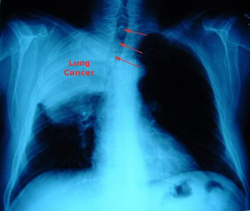

Διαφορετική η φύση του καρκίνου των πνευμόνων στις γυναίκες

Αθήνα: Αμερικανοί επιστήμονες ανακάλυψαν γονίδια που σχετίζονται με το φύλο, με συνέπεια ο καρκίνος των πνευμόνων στις γυναίκες να είναι δραματικά διαφορετικός και λιγότερο πολύπλοκος σε σχέση με τους άνδρες.